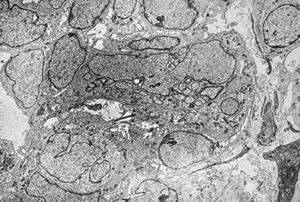

F,8y. | metachromatic leukodystrophy - n.suralis

F,25y. | metachromatic leukodystrophy - n.suralis

F,8y. | metachromatic leukodystrophy - n.suralis

F,25y. | metachromatic leukodystrophy - n.suralis

F,25y. | metachromatic leukodystrophy - n.suralis